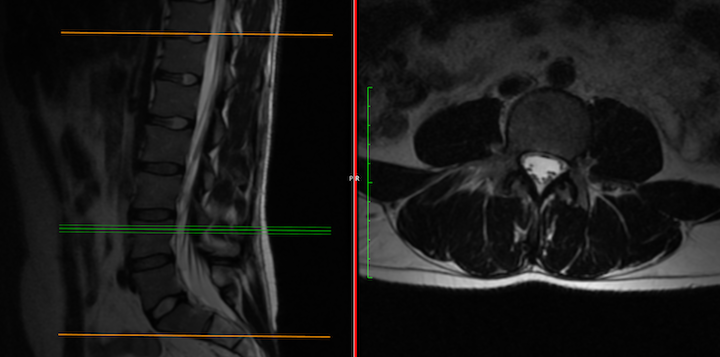

Does this patient have obvious arachnoiditis?

Pt. has had four MR of the the thoracic spine, all yielding an interpretation of visible soft tissue masses at T8 & T11. Pt. also has degenerative changes, moderate foramenal stenosis at L5/S1, L4/L5...and the last neurological rad providing interpretation of lumbar MR, noted pt has arachnoiditis, with "empty sac sign"...moderate to severe.

Given the limited treatment options available for arachnoiditis or the adhesive version, I am curious as to what others thoughts are on this Pts. imaging.... any eyes would be appreciated.